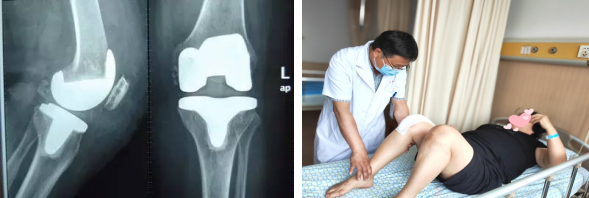

膝关节置换手术目前来说已经是非常成熟的治疗方法,主要是把膝关节表面已经磨损成坑坑洼洼的软骨切除,替换成金属的假体和高分子聚乙烯的耐磨垫片。

简单来说就是将患者关节表面被破坏的部分切除一层,再将同样厚度的人工关节装在病变切除处的表面,所以确切的说应该是膝关节表面置换术。能有效缓解膝关节疼痛,极大提高患者的生活质量。

因为手术具有一定的创伤,所以患者进行关节置换术后会存在一段时间的疼痛不适。人们之所以害怕做手术,是误以为把整个膝盖都换掉,事实上创伤并没有想象中那么大。